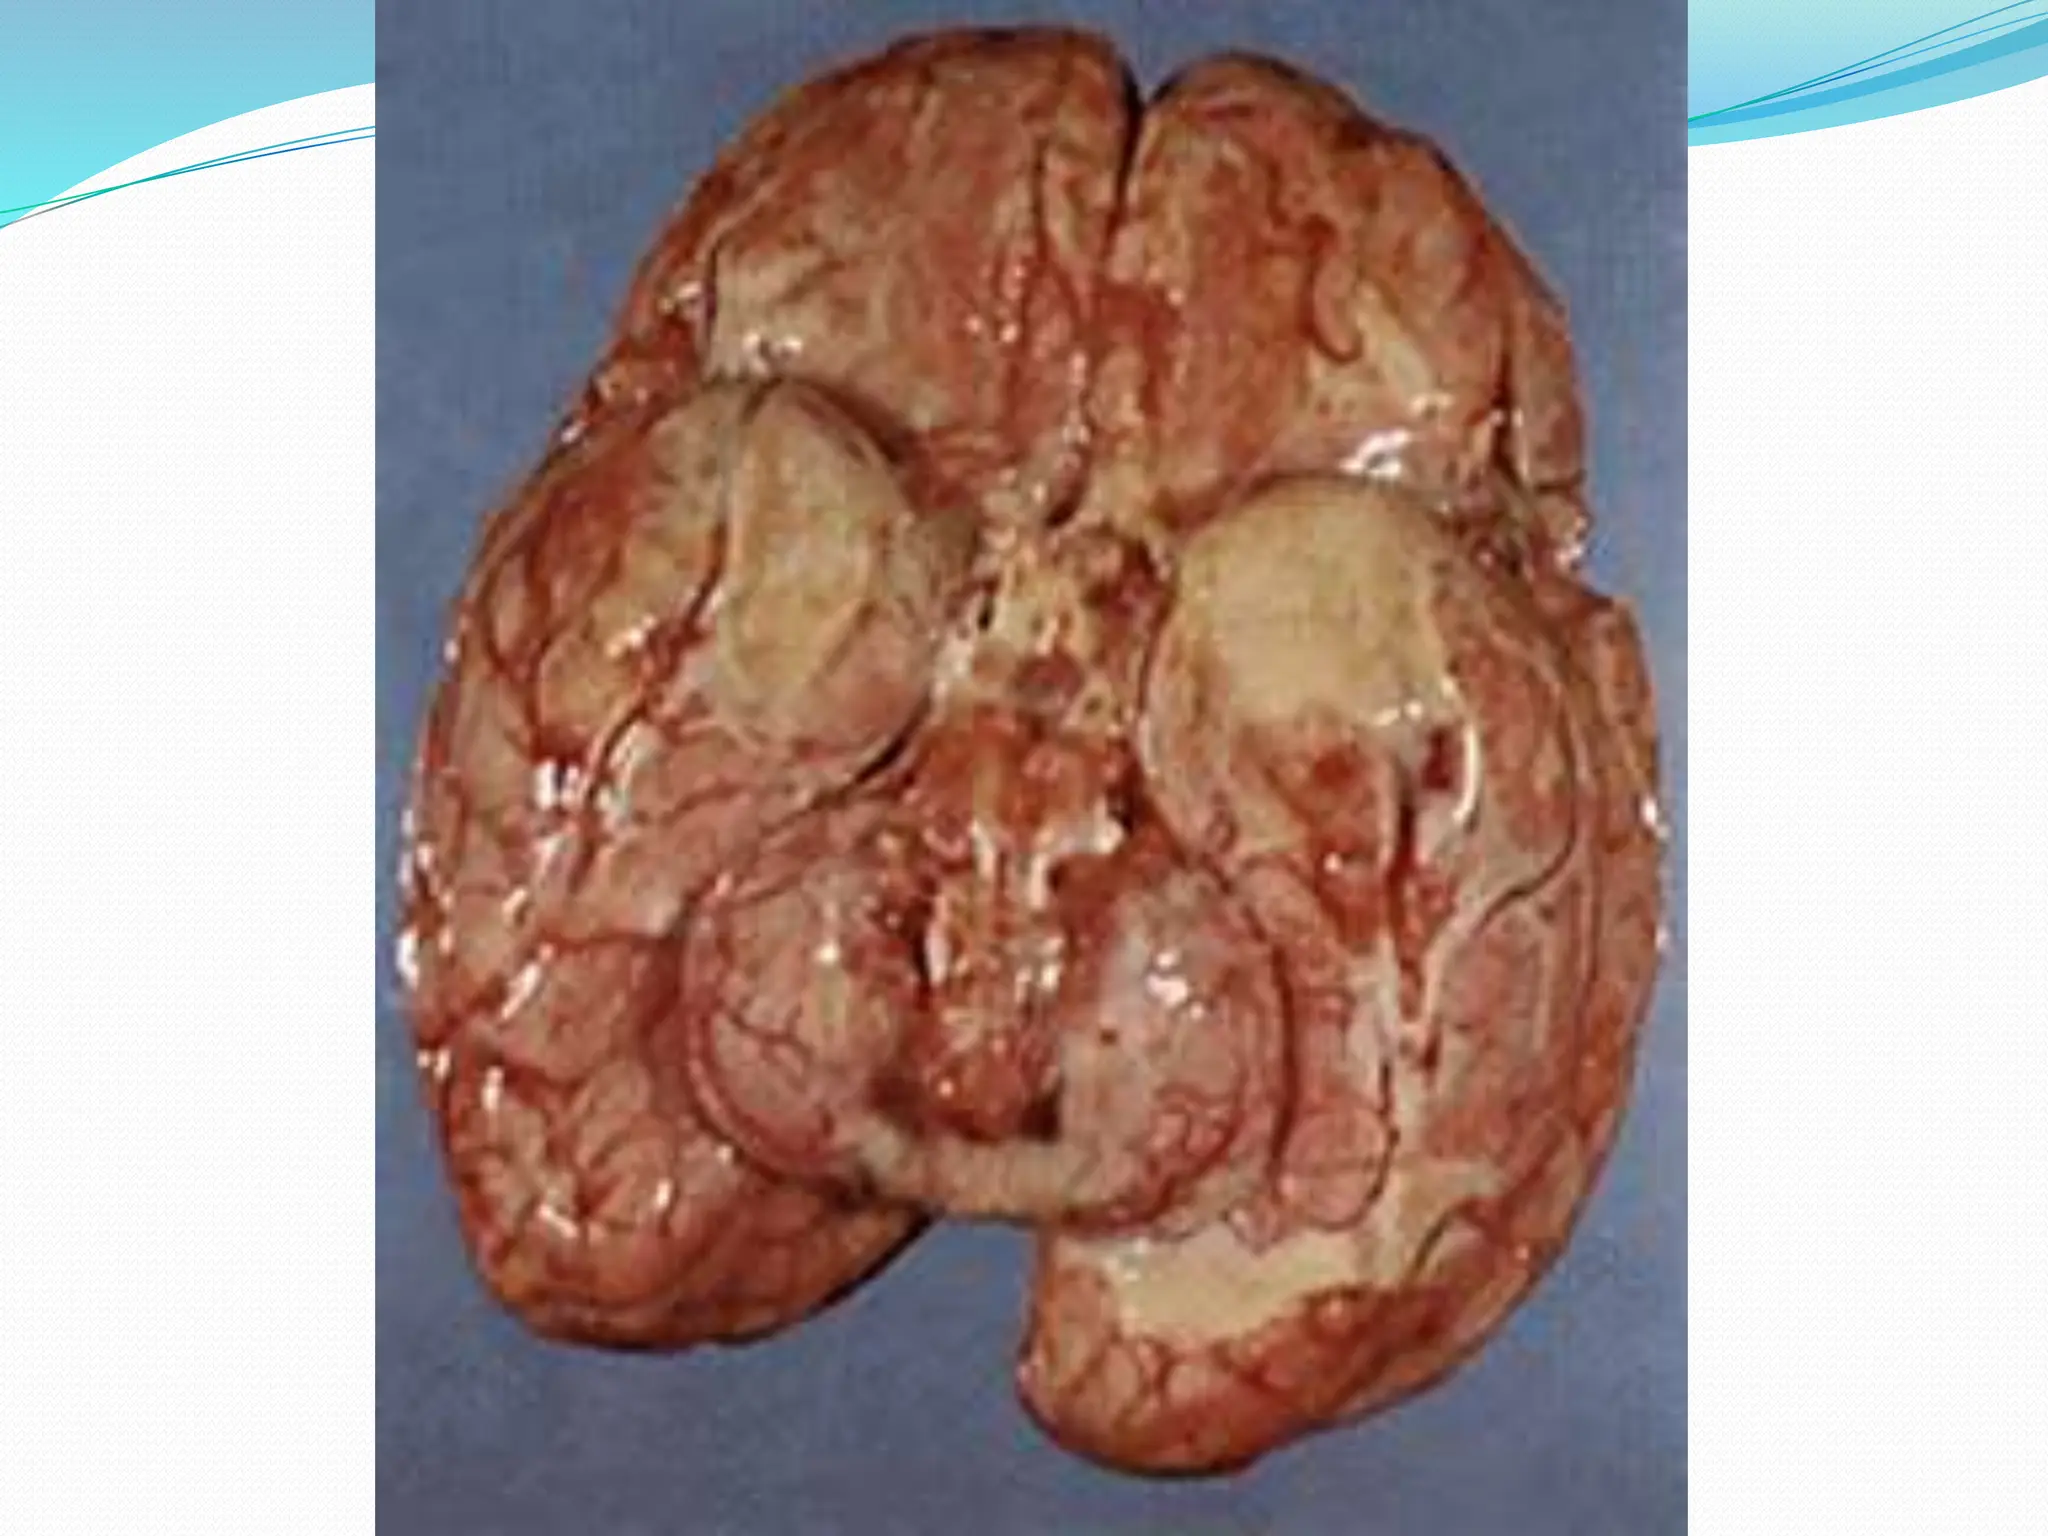

ACUTE MENINGITIS

 Chronic bacterial meningoencephalitis

 Gross: gelatinous or fibrinous exudate in S.A. space

Diffuse meningoencephalitis:

 Discrete, white granules over leptomeninges

 Mixture of lymphocytes, plasma cells & macrophages.

 Granulomas, caseous necrosis, giant cells.

 Obliterative endarteritis.

 Acid fast stains – bacilli.